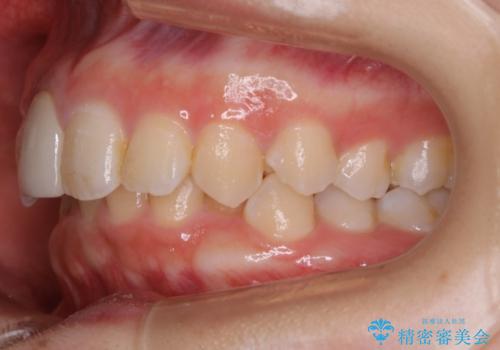

- 前歯の並びを気にして来院。

右上の2番目の前歯のセラミックが小さく、並びが気になるとのことでした。

また、右下の歯が生まれつき少なく、隙間が空いている状態でした。

右上の2番目の前歯が奥に入っている状態で、かぶせてあったため左に比べて短いセラミックになってしまっていました。